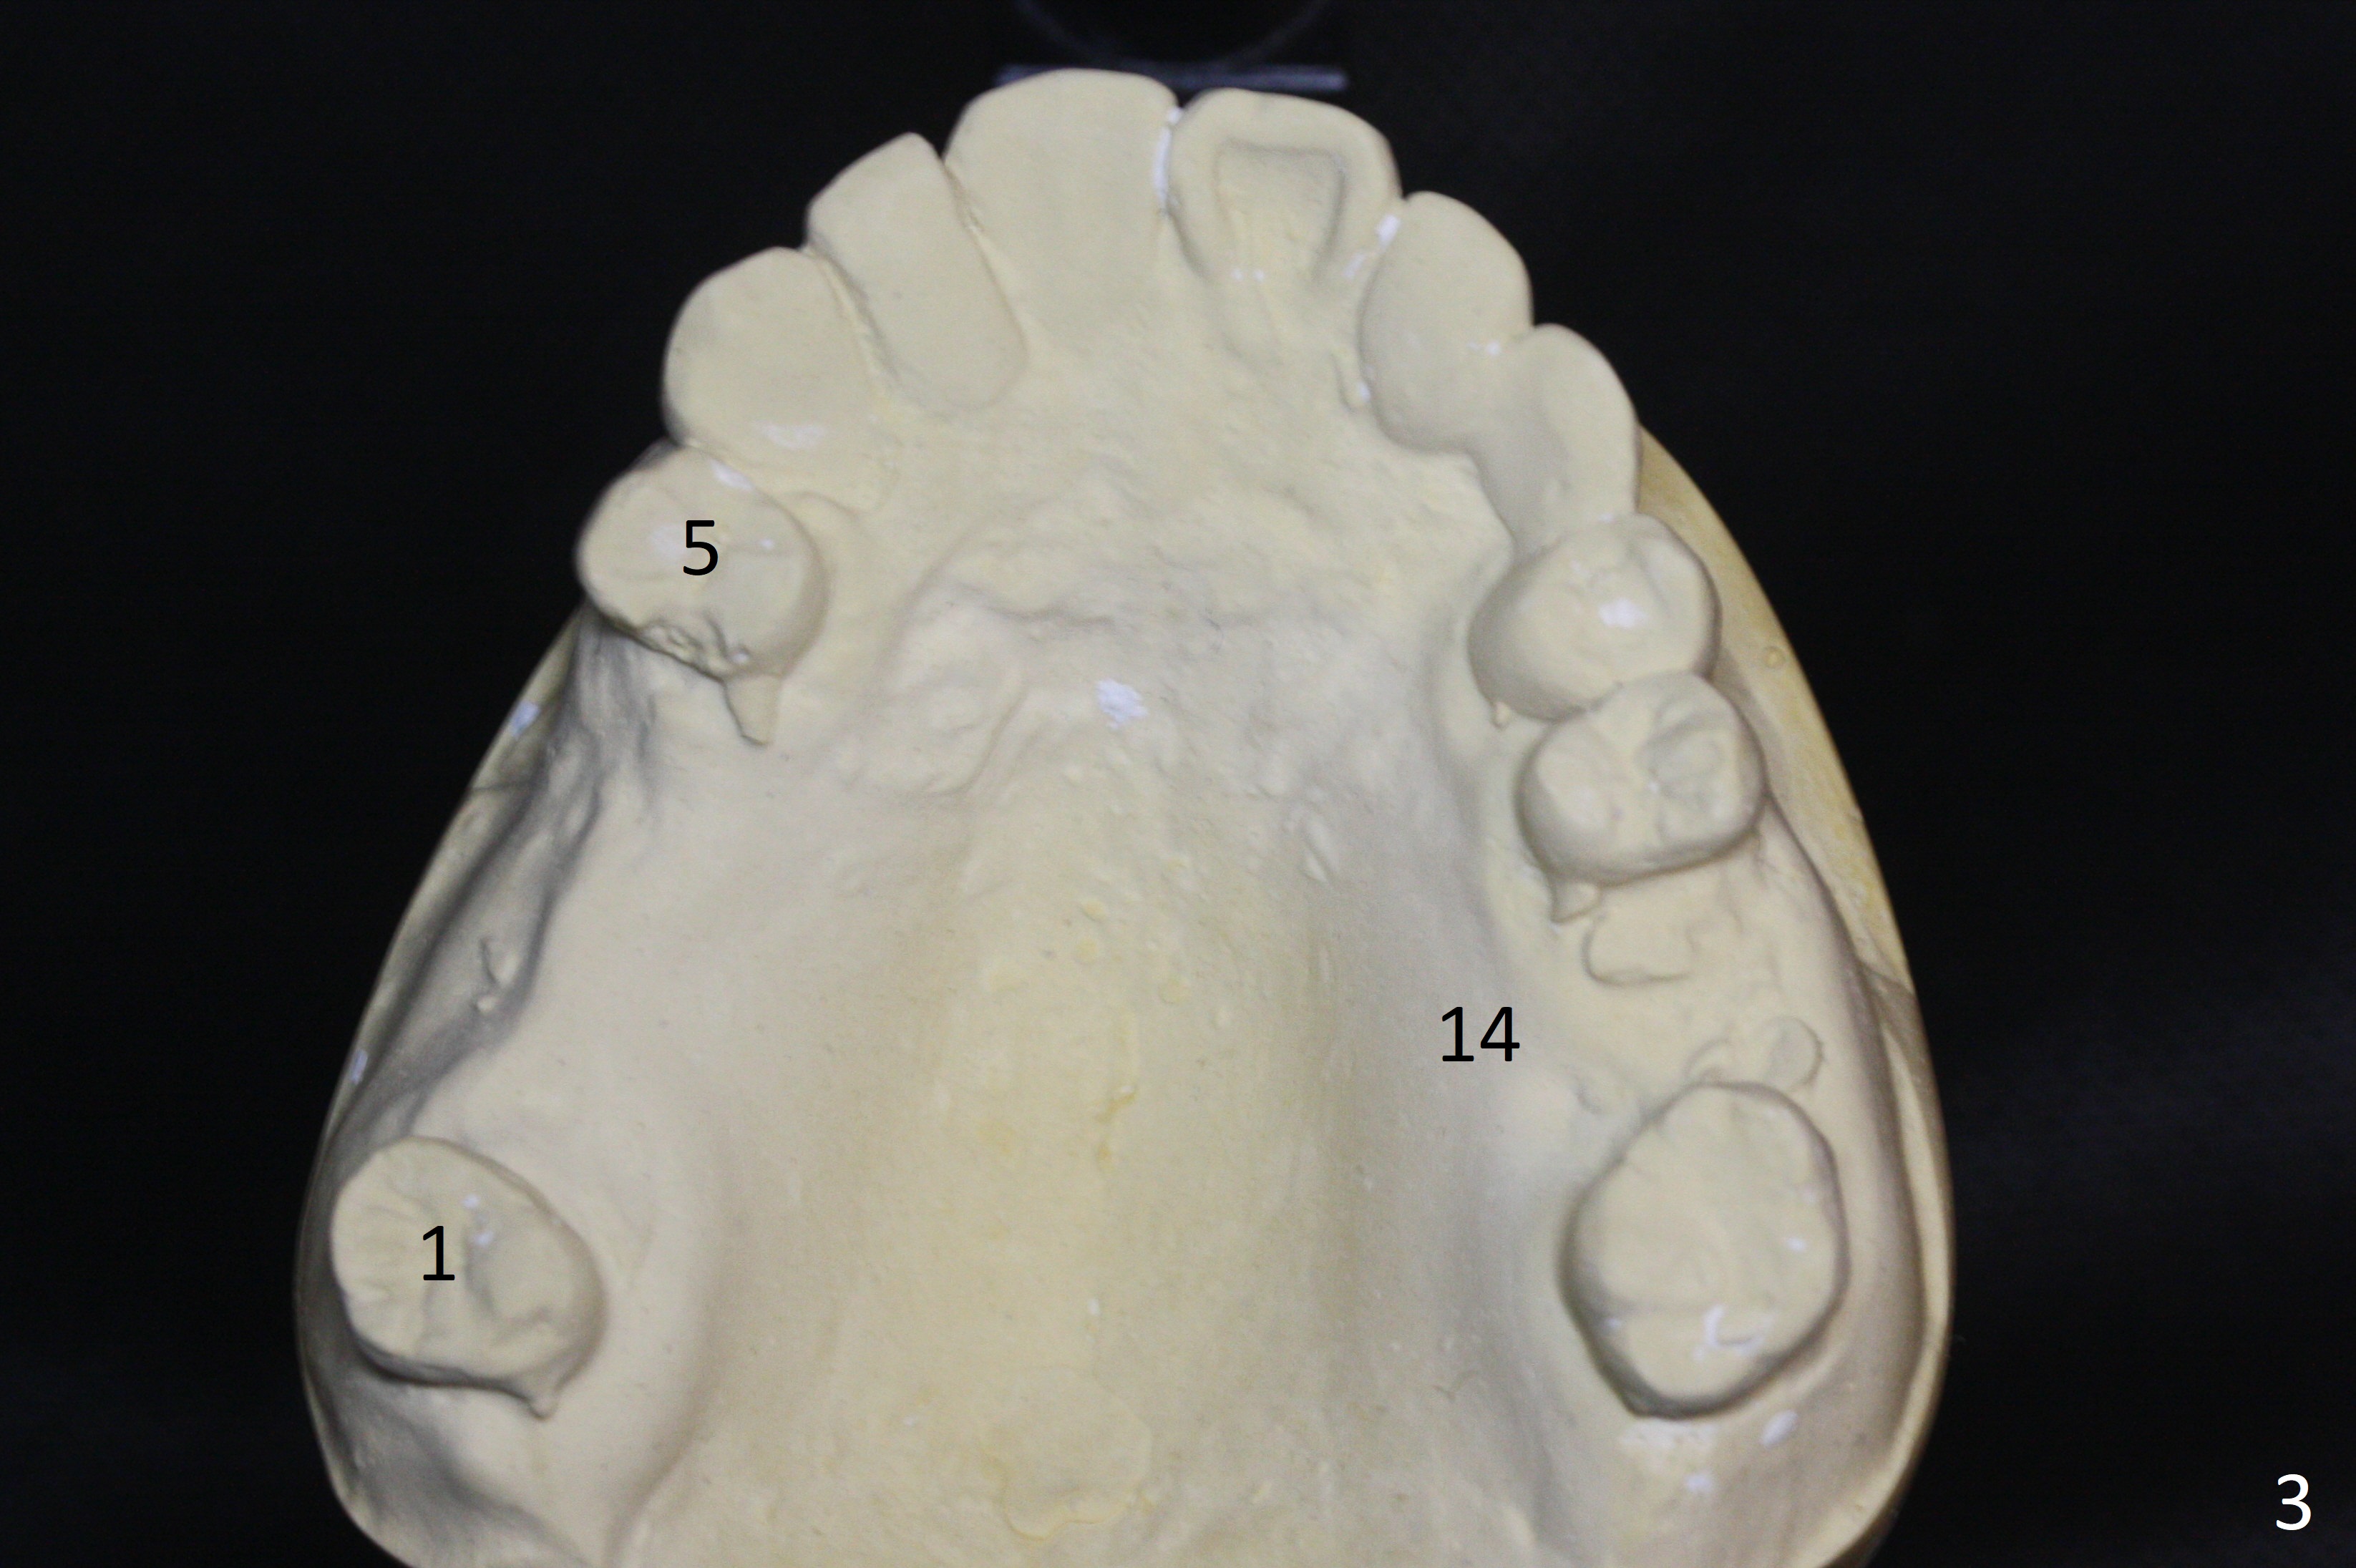

A 54-year-old man is 5 years post liver cancer surgery. After his platelet count returns normal, he wants to take care of his teeth. Most of his molars (#14, 19, 30,31) need extraction and implant placement (Fig.1-4). Although the 2nd premolars on the right are missing (Fig.1,3,4), it seems appropriate to establish 2 molar occlusion on the right (Fig.5,7,8) and 1 on the left (Fig.6,7 (because of #15 supraeruption (Fig.2 arrow))) . Since the residual roots in the lower right quadrant are irritating, implant placement will be done first (Fig.11, Clindamycin), followed by #2,3 (Fig.10) and 14(Fig.12 IBS) and 19 (Fig.12). Use IS drills and 4 and 5 mm stoppers to start osteotomy at #30 and 31, respectively.